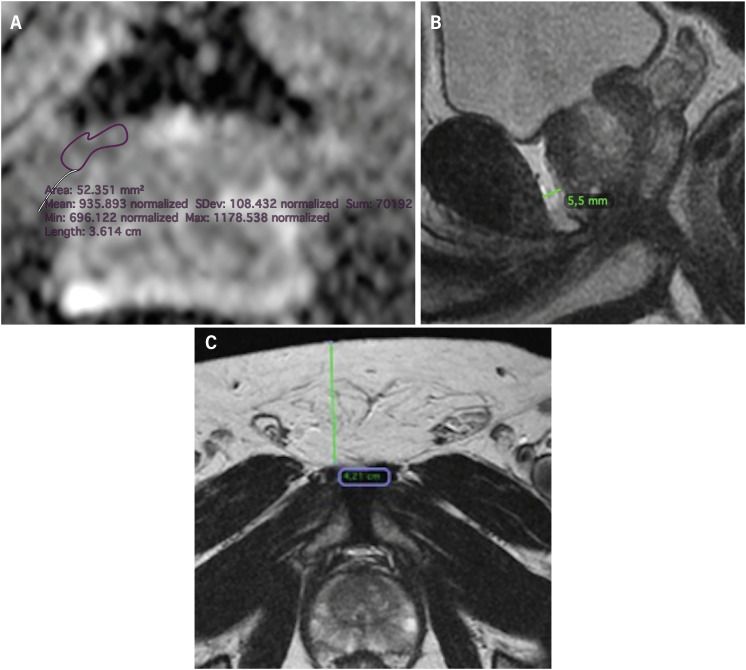

Material and methods: This retrospective study included patients with histologically proven PCa who underwent 3.0T MRI between July 2016 and June 2018. Clinical and demographic data collected included PSA, PSA density (dPSA), ISUP grade, clinical and pathological staging, and treatment details. MRI-derived parameters were assessed by an experienced radiologist, who measured subcutaneous and periprostatic fat thickness, and calculated ADC values from ROI plots in periprostatic fat. Clinical and MRI parameters were analyzed for associations with biochemical recurrence, systemic metastasis, and PCa-related mortality.